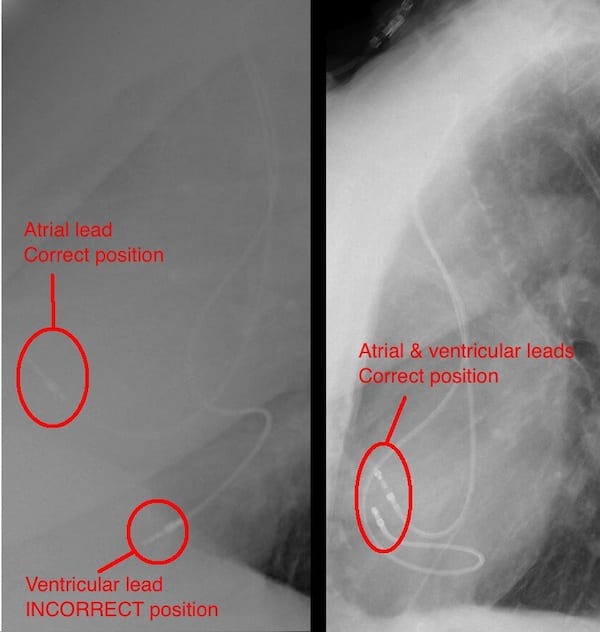

The following PA and lateral CXR are taken from an unrelated case with appropriately placed pacing leads in the right atrium and right ventricle.

- Note the PA CXR appearance is not too different from the PA CXR in our case of lead misplacement

- Note on the lateral CXR both leads are placed anteriorly signifying right sided placement.

- Side-by-side comparison of cardiac silhouettes. Abnormal on left. Normal on right.